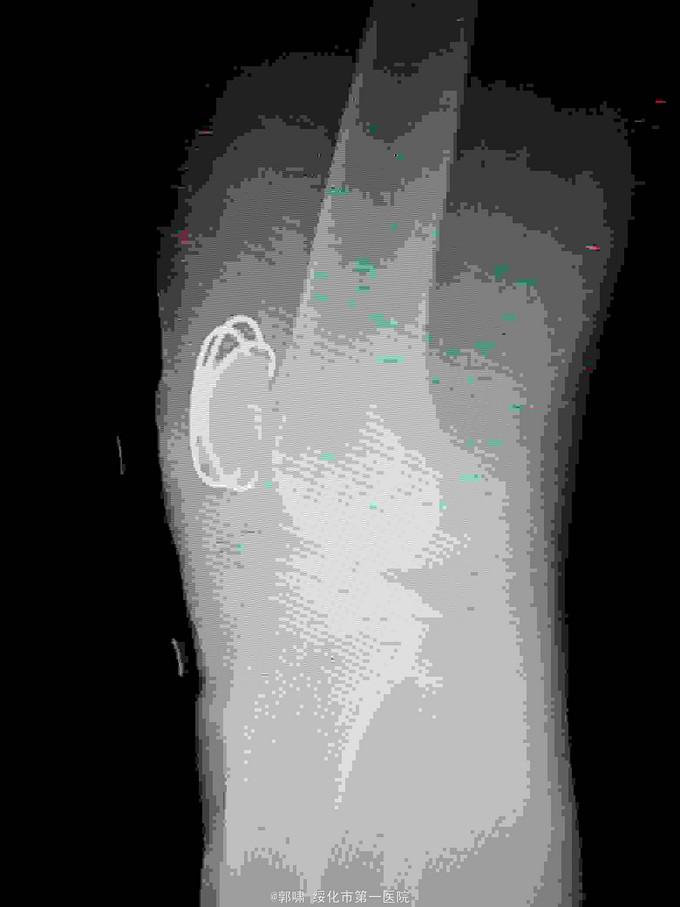

左膝关节摔伤,肿胀,畸形,活动受限一小时。收入院。患者于一小时前滑倒摔伤。当即倒地,左膝关节肿胀,畸形不能行走。门诊拍片示:左膝关节髌骨骨折,断端移位。门诊以左髌骨骨折收入院。

左膝关节肿胀,局部畸形,不能下地行走。浮髌试验阳性。拍片示:左髌骨骨折。

诊断:左髌骨骨折。立即予以腰麻下行切开复位内固定术。术中复位骨折,缝合筋膜,冰水浸泡髌骨爪约10分钟。待髌骨爪变软。选取合适大小的髌骨爪。应用记忆合金髌骨爪内固定。立即用40°温盐水热敷局部。使记忆合金加速抓紧。环抱。缝合爪齿二道,防止脱落。缝合关节囊,韧带组织。术毕。

应用记忆合金髌骨爪内固定髌骨骨折。手术时间基本在20----30分钟内都可以完成。局部损伤小。固定牢靠,确实。患者二个月就可以下地负重活动。具体手术技巧。一是髌骨爪提前用冰盐水侵泡10分钟左右。待记忆合金变软即可使用。二。固定牢靠后立即用40°温盐水热敷。使其快速抓紧。三,缝合爪齿,防脱。四如有粉碎,小的骨块可以缝合筋膜固定。有大骨块,最好环扎钢丝,或穿针固定,有时穿骨隧道钢丝捆扎。效果也不错。只要做到以上几点。安全无忧了!以下是以前做的片子。可以看一看。